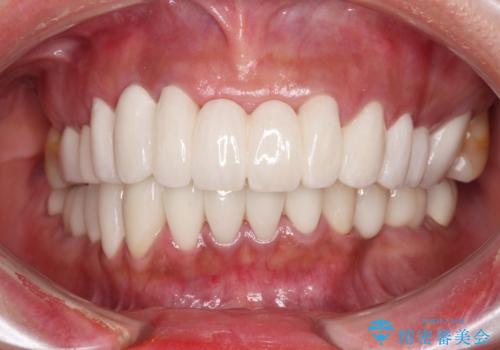

抜歯が必要な左右の奥歯 ブリッジとインプラントによる奥歯の補綴治療

![[ 欠損補綴 ] ブリッジとインプラントの症例 治療前](https://seimitsushinbi.jp/wp/wp-content/uploads/2021/10/d680d397e015686572db595995781e12-500x350.jpg?v=1634192539)

![[ 欠損補綴 ] ブリッジとインプラントの症例 治療後](https://seimitsushinbi.jp/wp/wp-content/uploads/2021/10/82c7cc111177152f4f990e0f169487f7-500x350.jpg?v=1634192579)